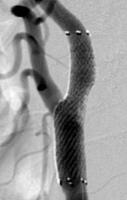

頸動脈ステント留置術

術前

術後

狭くなり血流が悪くなってしまった頸動脈に、ステントと呼ばれる金属性のメッシュ状の筒を留置して血管を拡張させ、血流を回復させる手術です。